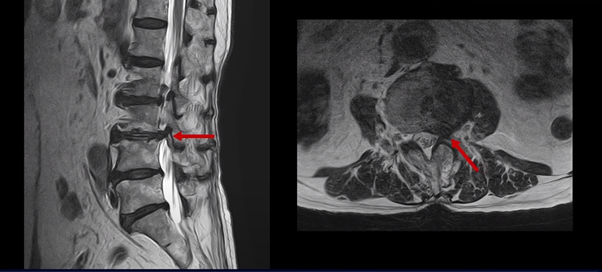

이 두 마디가 왼쪽 증상, 특히 허벅지 통증을 일으키는 원인으로 보입니다. 이렇게 여러 마디가 안 좋을수록, 또 고령일수록 수술하기가 더 까다로워지는데 또 큰 문제는 이 환자분은 근감소증이 심하게 진행된 상태로, 여기 MRI에서 보시다시피 허리 하부의 기립근 근육이 전부 지방으로 변해버려 근육 자체가 거의 없는 상태인 것입니다.

근육이 없는 근감소증 환자는 척추수술 후 예후가 더 안 좋은 것으로 알려져 있기 때문에 상담하신 정형외과에서도 수술 권유를 안 한 것으로 보입니다.